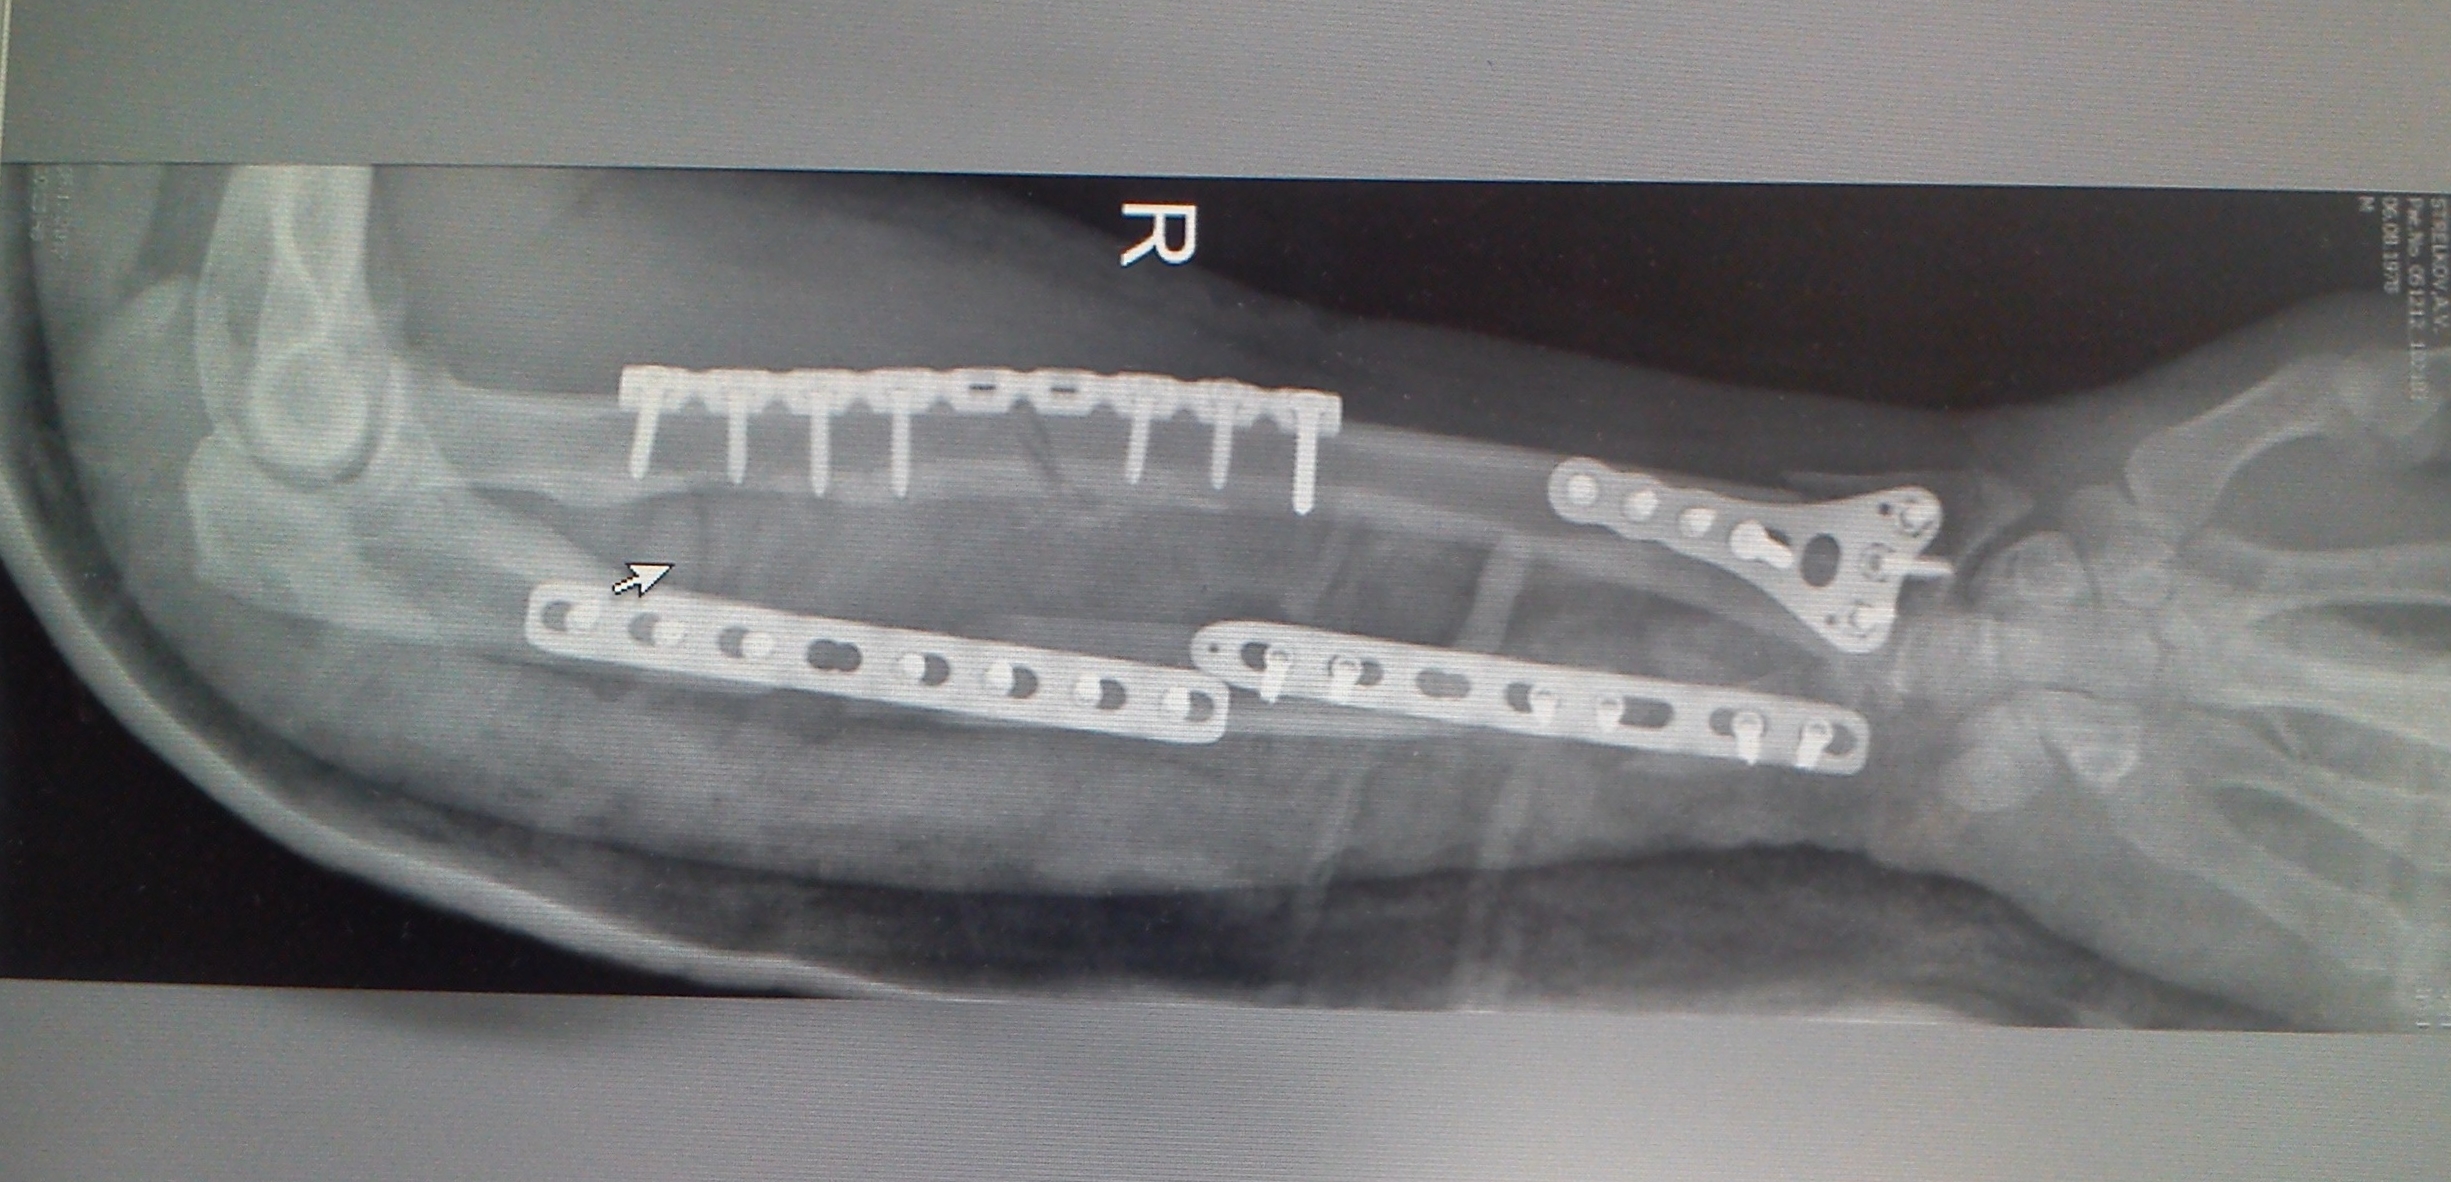

Медицинские снимки: Пластина в левом предплечье